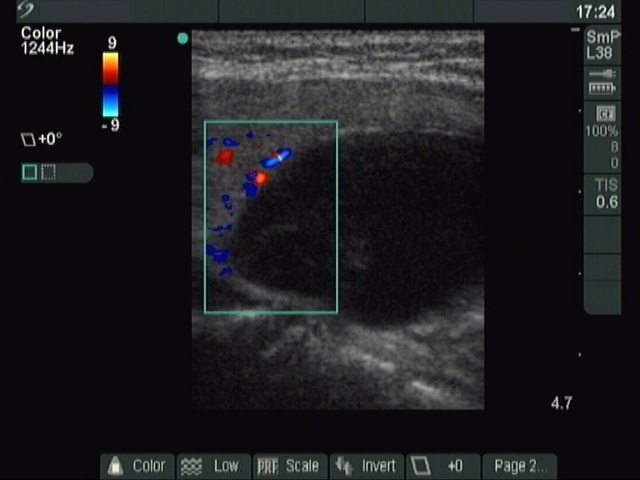

Initial investigation (ultrasonographic picture 3)

Left lobe, longitudinal view, color Doppler mode. Type 2 vascular pattern.